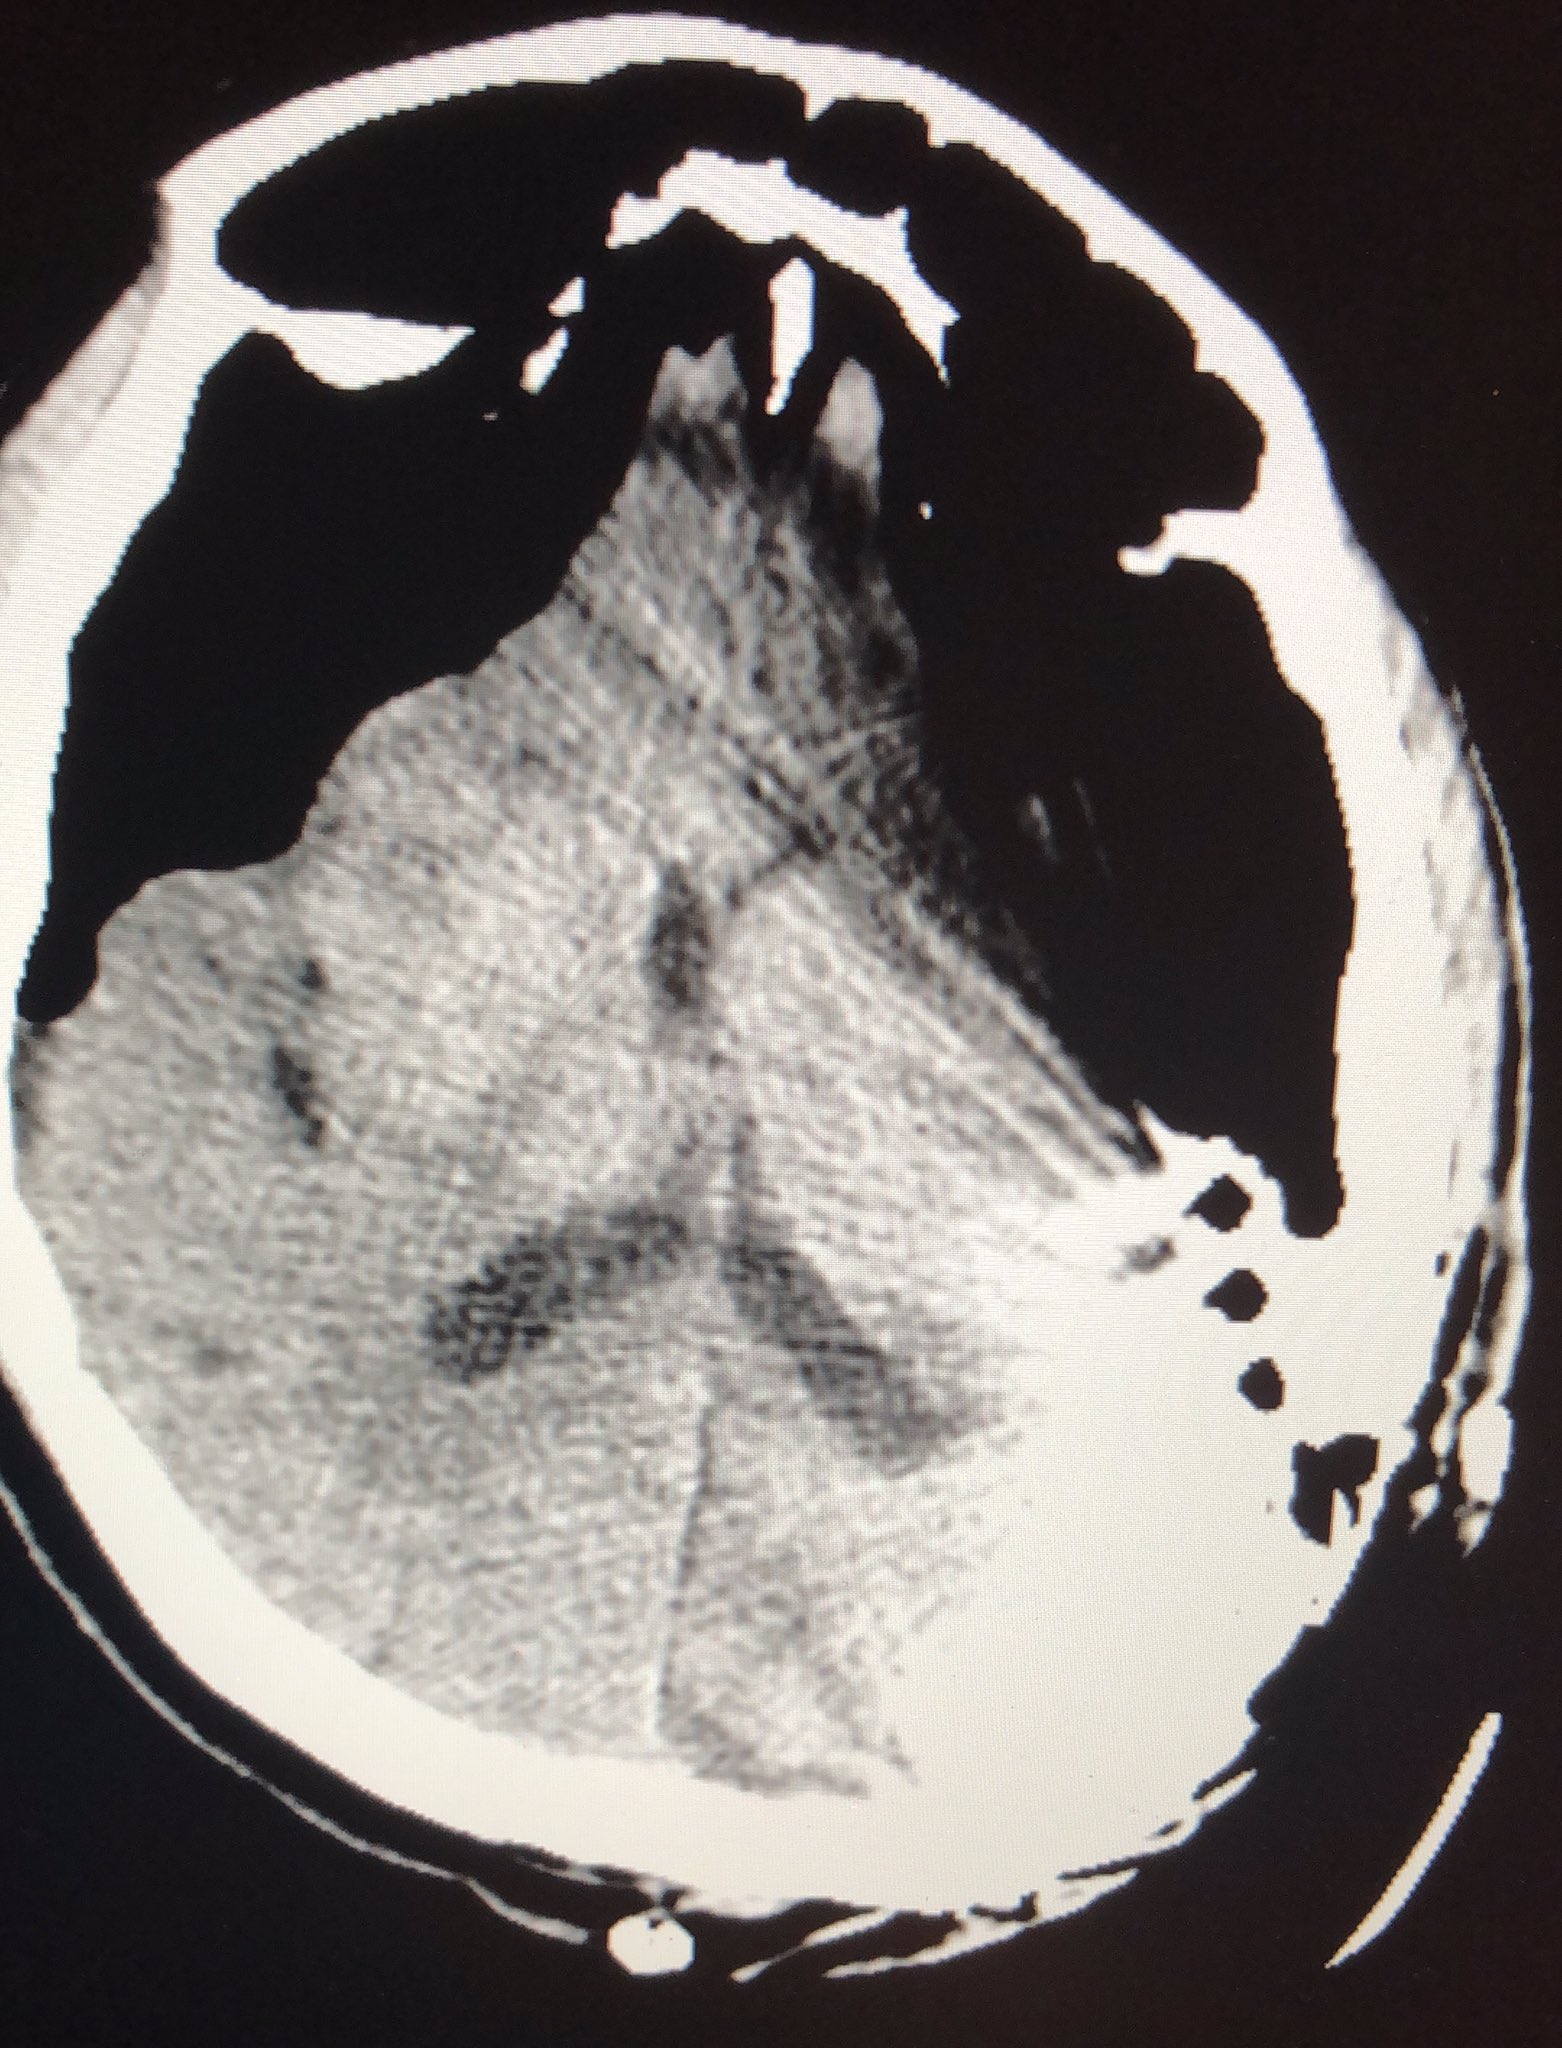

Note that subdural air separates and flattens the frontal lobes while widening the interhemispheric space.

1department of emergency medicine, chi mei medical center, tainan, taiwan. A rare case of spontaneous pneumocephalus associated with nontraumatic. The journal of emergency medicine, vol. The ct scan typically shows the mount fuji sign (the name is derived from a volcanic mountain in japan that is known for its symmetrical.